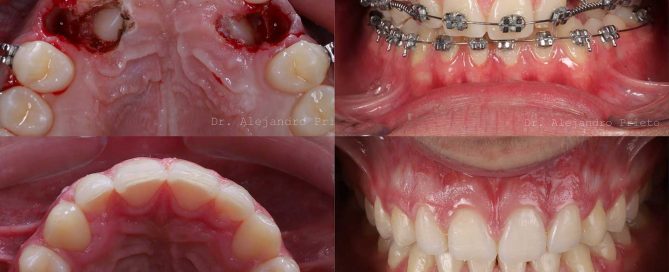

Dientes caninos incluidos en el paladar